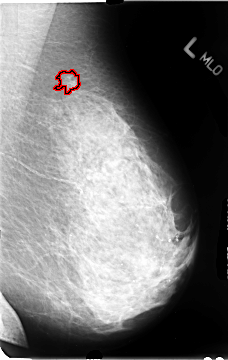

B_3078_1.LEFT_MLO

FILE: B_3078_1.LEFT_MLO.OVERLAY

TOTAL_ABNORMALITIES 1

ABNORMALITY 1

LESION_TYPE MASS SHAPE IRREGULAR MARGINS ILL_DEFINED-SPICULATED

ASSESSMENT 4

SUBTLETY 3

PATHOLOGY MALIGNANT

TOTAL_OUTLINES 1

BOUNDARY